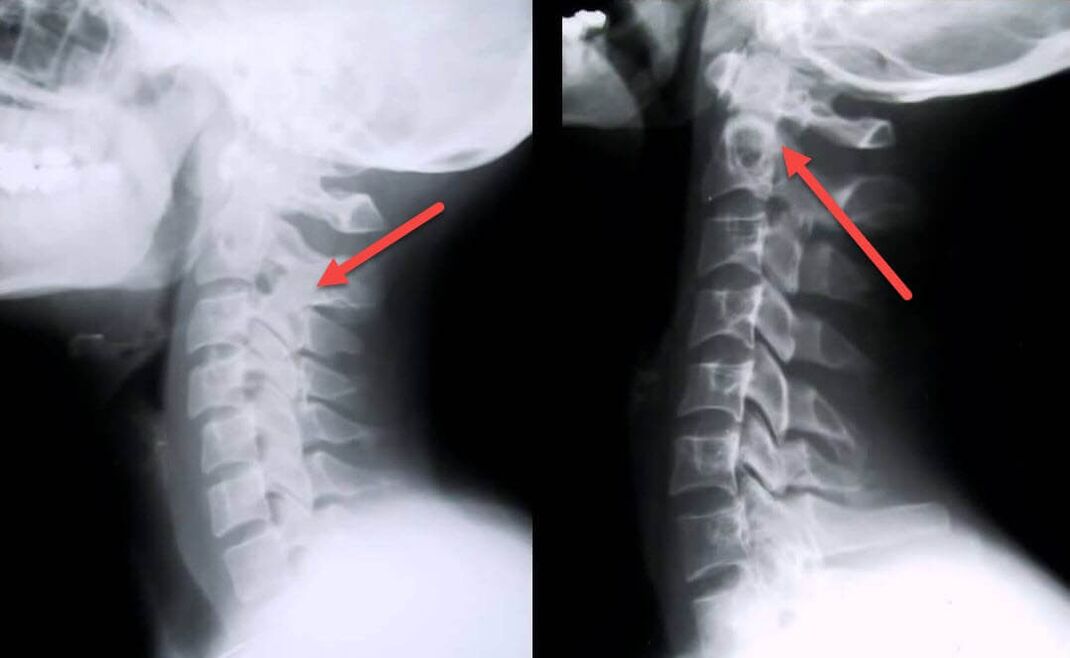

The most informative diagnostic procedure is radiography.Grade 1 pathology corresponds to grade 1 or 2 radiological stage.The resulting images visualize the typical symptoms of the disease.

| X-ray staging of grade 1 cervical osteochondrosis | Feature flag |

|---|---|

| first stage | Small changes in the curvature of the spine in the neck, affecting one or more segments |

| second stage | Slight thickening of the intervertebral discs, deformation of the uncinus, straightening of the lordosis, and slight growth of the bone structure |

Magnetic resonance imaging is sometimes needed to confirm the diagnosis.With it you can detect sterility, slow inflammatory processes and damaging degenerative changes in the intervertebral disc.